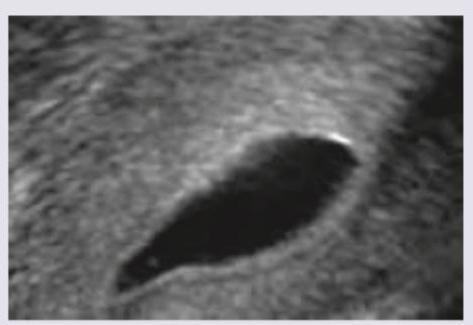

Explanation: ***Gartner cyst*** - The image shows a fluid-filled lesion in the **anterolateral vaginal wall**, consistent with a Gartner's cyst, which is a remnant of the **Wolffian duct**. - This cyst is typically located along the course of the Gartner's duct and can be palpated or visualized during pelvic examination. *Rectocele* - A rectocele involves the **posterior vaginal wall bulging into the vaginal lumen** due to rectovaginal fascia weakness, where the rectum protrudes. - The image clearly depicts an anterior vaginal wall lesion, not a posterior one. *Nabothian cyst* - **Nabothian cysts** are retention cysts located on the **cervix**, resulting from blocked cervical glands. - The lesion in the image is located in the vagina, not on the cervix. *Submucous fibroids* - **Submucous fibroids** are **uterine leiomyomas** that protrude into the endometrial cavity, originating from the myometrium. - The image shows a vaginal lesion, not a uterine pathology.